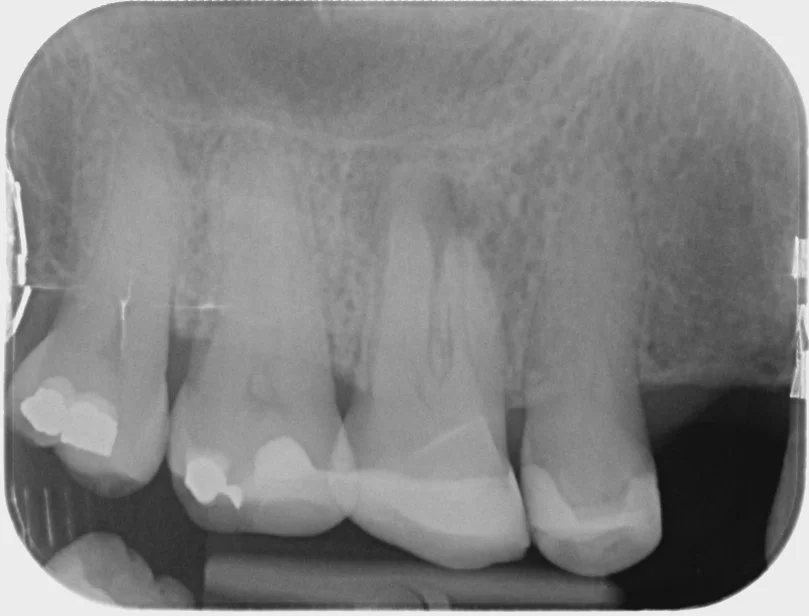

Dental Implants